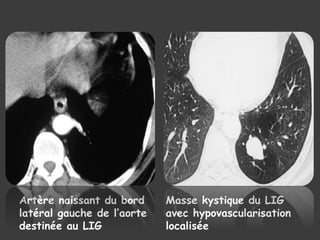

LE SCANNER THORACIQUE

 Masse kystique ou tissulaire

 Anomalies de perfusion en périphérie

 TDM+ PDC ====> EXAMEN DE CHOIX

artère systémique + étude du retour

Artère naissant du bord

latéral gauche de l’aorte

destinée au LIG

Masse kystique du LIG

avec hypovascularisation

localisée

Vaisseau de gros calibre naissant

de la face latérale gauche de

l’aorte descendante